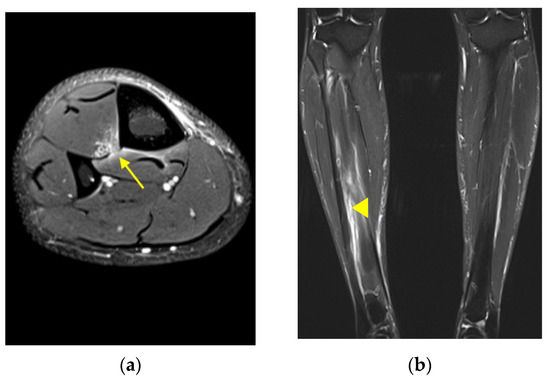

Case 4: A 21-year-old male collegiate football player presented with left knee and leg pain after direct helmet hit to the leg. Physical exam was notable for tenderness to palpation about the posterior knee. Radiography was unremarkable. MRI revealed a focal 1 cm defect of the IOM at the level of the proximal third of the tibial diaphysis (Figure 2).

Figure 2. Case 4. Axial proton density fat-saturated MR image from a 21-year-old man with focal defect of the tibiofibular IOM at the level of the proximal third of the tibial diaphysis (yellow arrow).